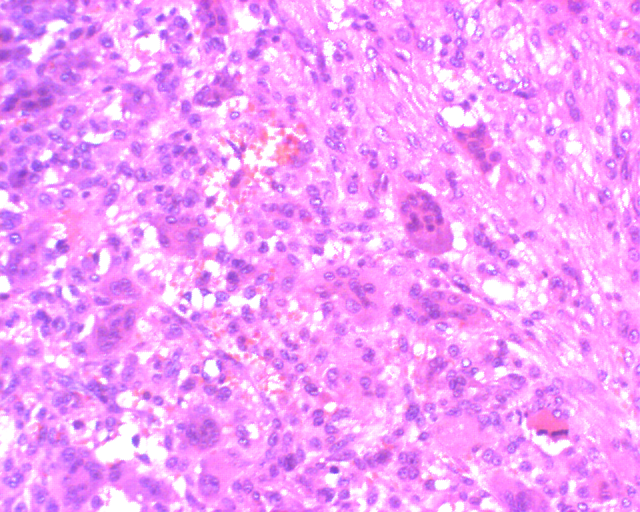

2.镜下

组织学特征性改变为圆形、卵圆形、多角形或梭形的单核基质细胞,以及均匀分布其中的破骨细胞样巨细胞。这种巨细胞体积可以很大,核的数量可达到50~100个,基质细胞的核与巨细胞的核形态相似,染色质疏松,1~2个小核仁,胞质界限不清,细胞间含有少量 胶原,核分裂象易见,每10个高倍视野可见2~20个不等,但无病理性核分裂。

大的特征性破骨细胞样巨细胞并非肿瘤细胞这一观点现在已基本被接受,作为肿瘤性成分的单核基质细胞被认为是来源于原始间充质细胞(primitive mesenchymal stromal),这种单核细胞在瘤组织中数量较少,其表达的RANKL可刺激破骨细胞前体细胞向破骨细胞转化和成熟。

在具备上述基本特征的基础上,骨巨细胞瘤可分为多种类型。在一些病例,单核细胞形态更趋向于梭形,并可以排列成车辐状结构。通常情况下,可存在少量泡沫细胞,在少数病例,由于大量泡沫细胞的存在,产生类似纤维组织细胞瘤的改变。在大约10%伴发继发性动脉瘤样骨囊肿的病例中,可出现纤维化区域。肿瘤中可有小灶性的新生骨形成,特别是在发生病理性骨折或骨活检术后的病例中。当病变扩展至软组织中或转移至肺组织中时,组织学特征与原发灶相同,并且经常可以见到外周反应性骨壳。在1/3的病例中,一个显著的特征是存在血管内瘤栓,特别是在瘤体的周边部,但没有特殊的预后价值。在体积较大的病变中肿瘤坏死亦很常见。

图 6 组织学表现

图 19 组织学特点:瘤细胞呈梭形,似肉瘤样,可见较多核分裂。